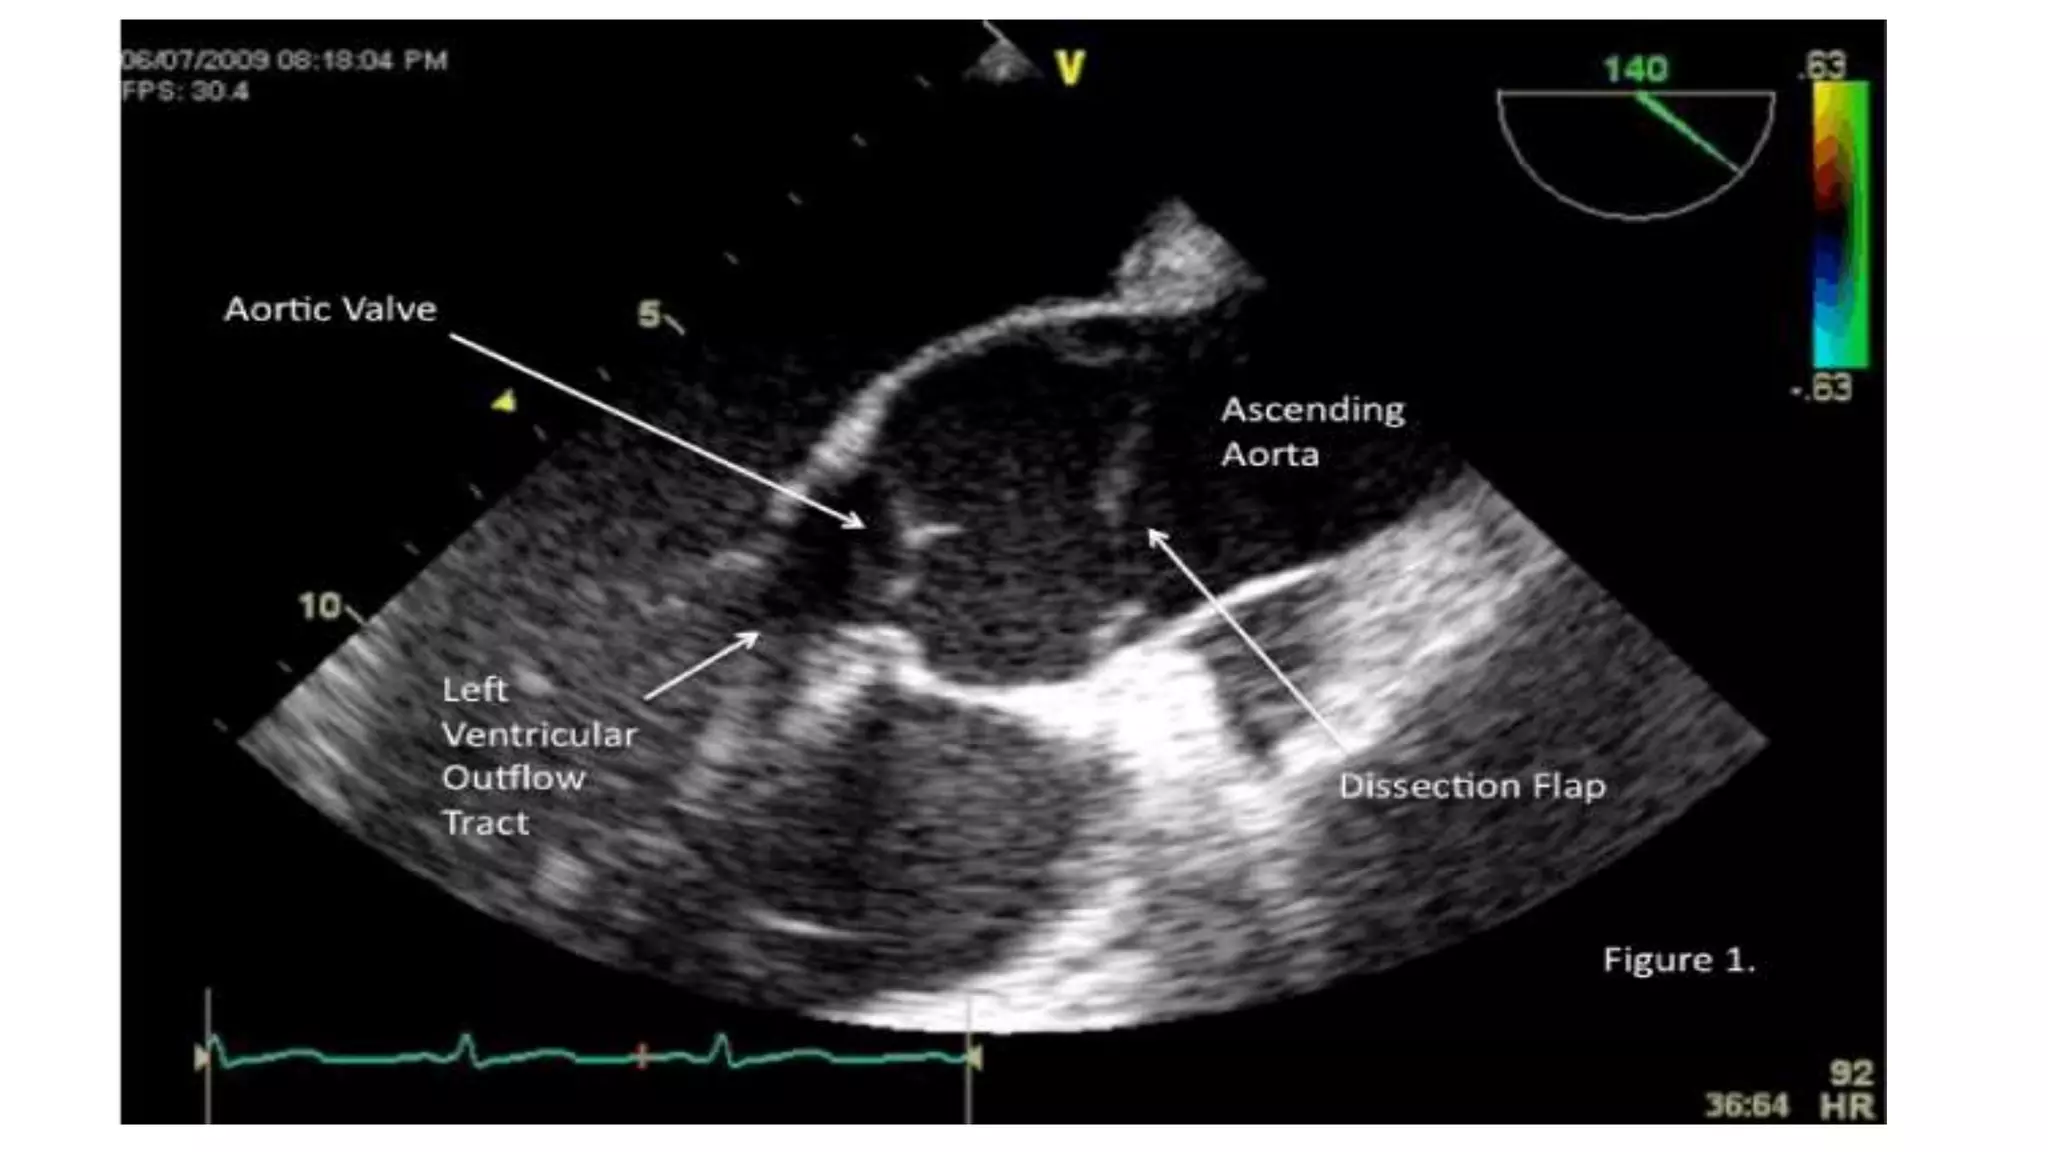

• Troianos et al described three cases of arterial dissection during CPB in

which TEE was found useful.

• Although provisional diagnoses were made on the basis of traditional

signs, TEE allowed assessment of the origin and extent of dissection.